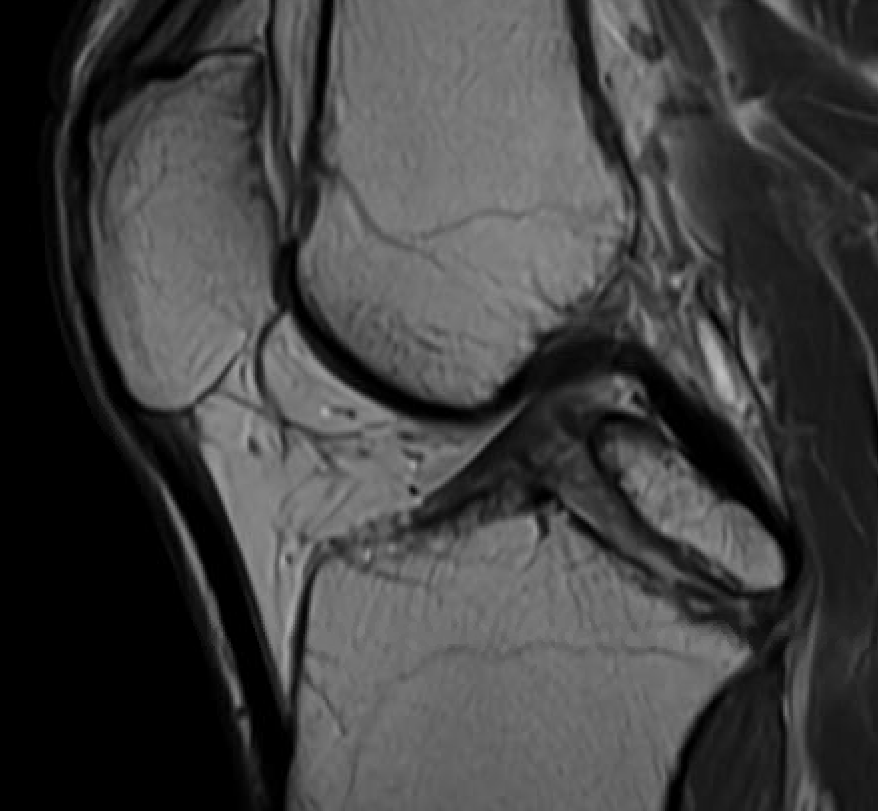

MRI

PCL completely torn

PCL midsubstance tear with lengthening

PCL tibial avulsion

PCL femoral avulsion